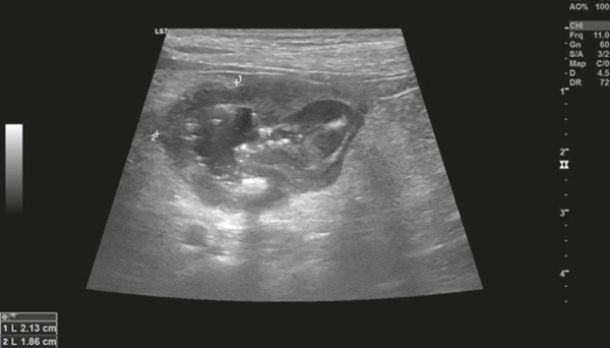

Diagnostic imaging forms a crucial part of clinical workup. Abdominal radiography might not be helpful as the changes in the gastrointestinal tract associated with AL depend on the disease severity, but we can observe a loss of detail or mass effect either due to the gastrointestinal mass and/or lymphadenomegaly or, less often, due to free abdominal fluid. Abdominal ultrasound is more commonly used. The most frequent ultrasonographic abnormality observed is abnormal wall layering with or without concurrent increase in wall thickness (Figure 1). The extent of wall changes can be highly variable in dogs with intestinal lymphoma. Where sonographic abnormalities were present, lesions have been characterised as: predominantly hypoechoic, focal or multifocal ulcerations, small hypoechoic nodules to larger masses (Figure 2) and enlarged abdominal lymph nodes (Figure 3). In some cases abdominal effusion may be present as well. The sonographic appearance of gastrointestinal lymphoma is variable and can overlap with that of a normal bowel, especially in cases of small cell or low-grade AL. Lastly, diffuse intestinal thickening has also been reported and it should be differentiated from enteritis. It is important to note that even when no ultrasonographical abnormalities are found, AL cannot be ruled out without obtaining biopsies of the gastrointestinal tract.